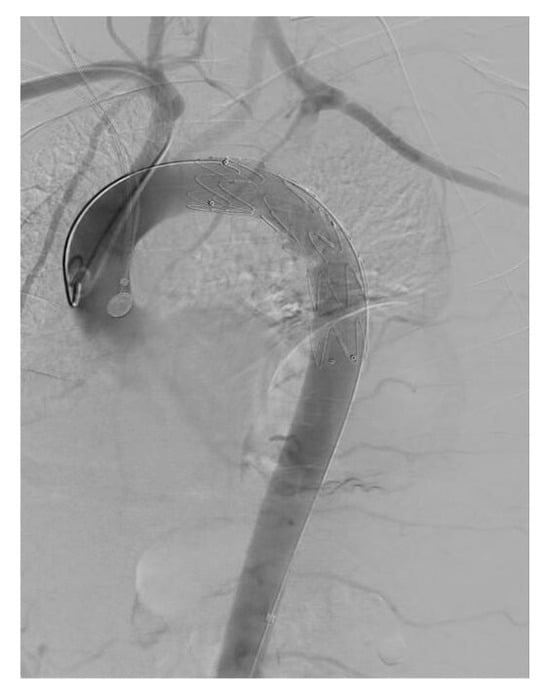

| True lumen | Severely compressed along descending thoracic and abdominal aorta | Re-expanded across thoracic segment | Stable re-expansion |

| Visceral perfusion | SMA and celiac from severely collapsed TL; R renal from FL | TL restored at visceral segment; R renal improved inflow | Full visceral patency; no endoleak |